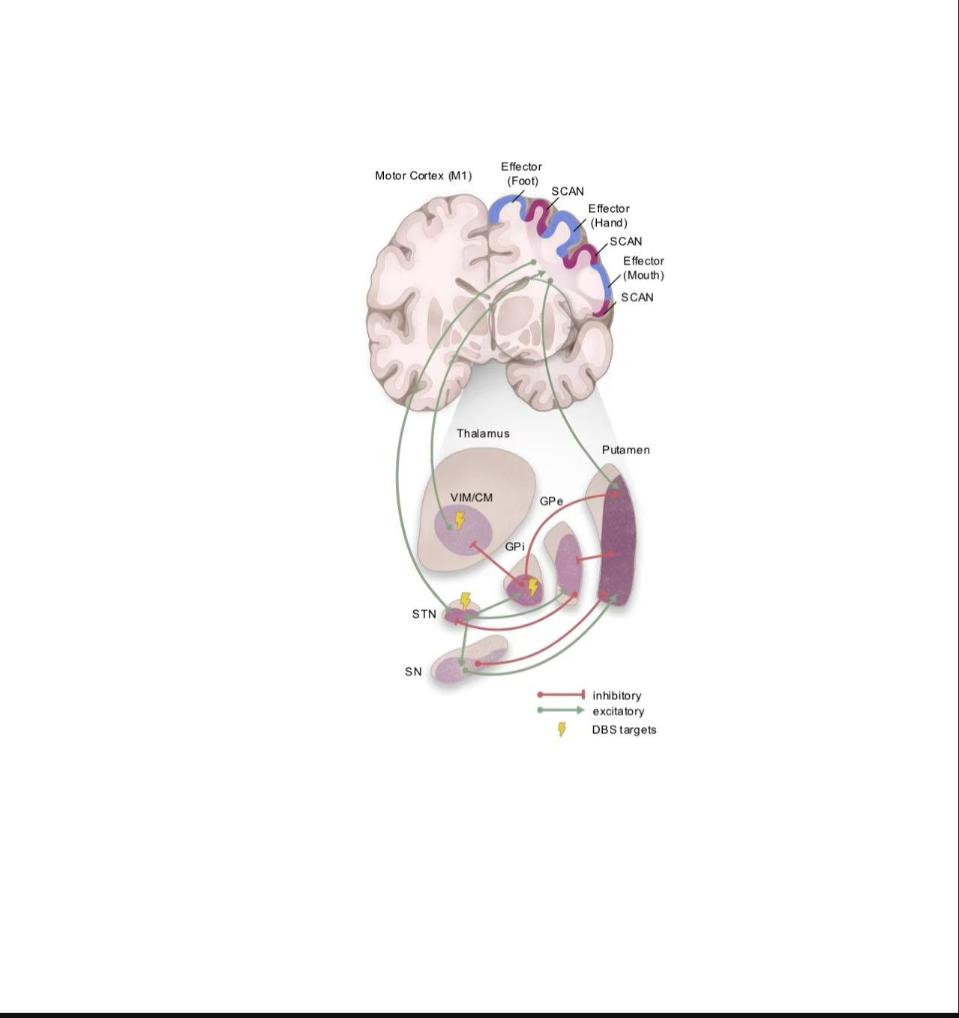

研究团队发现,帕金森病的核心问题是大脑中一个关键的脑网络——躯体认知网络发生严重功能异常。这一网络主要参与行动规划和协调,且和内脏活动等自主神经功能关系密切。在对超800例人脑影像数据的综合分析中发现,躯体认知网络与多个脑深部核团存在紧密连接,而这些连接在患者大脑中出现病态增强,这个环路的失调是患者出现各种复杂症状的重要原因。据悉,当前所有有效的帕金森病临床治疗手段,包括深部脑刺激手术和口服药物治疗,都是通过改善这个环路发挥作用。

帕金森病躯体认知环路示意图。(受访单位供图)

根据这一机制,刘河生团队自主研发出新一代精准脑环路刺激系统,实现了帕金森病治疗靶点的精准定位与无创治疗,设备已获批国家医疗器械注册证。临床结果显示,在治疗2周后,躯体认知靶点组的治疗有效率达55.5%,而刺激传统的大脑运动区有效率为22.2%。